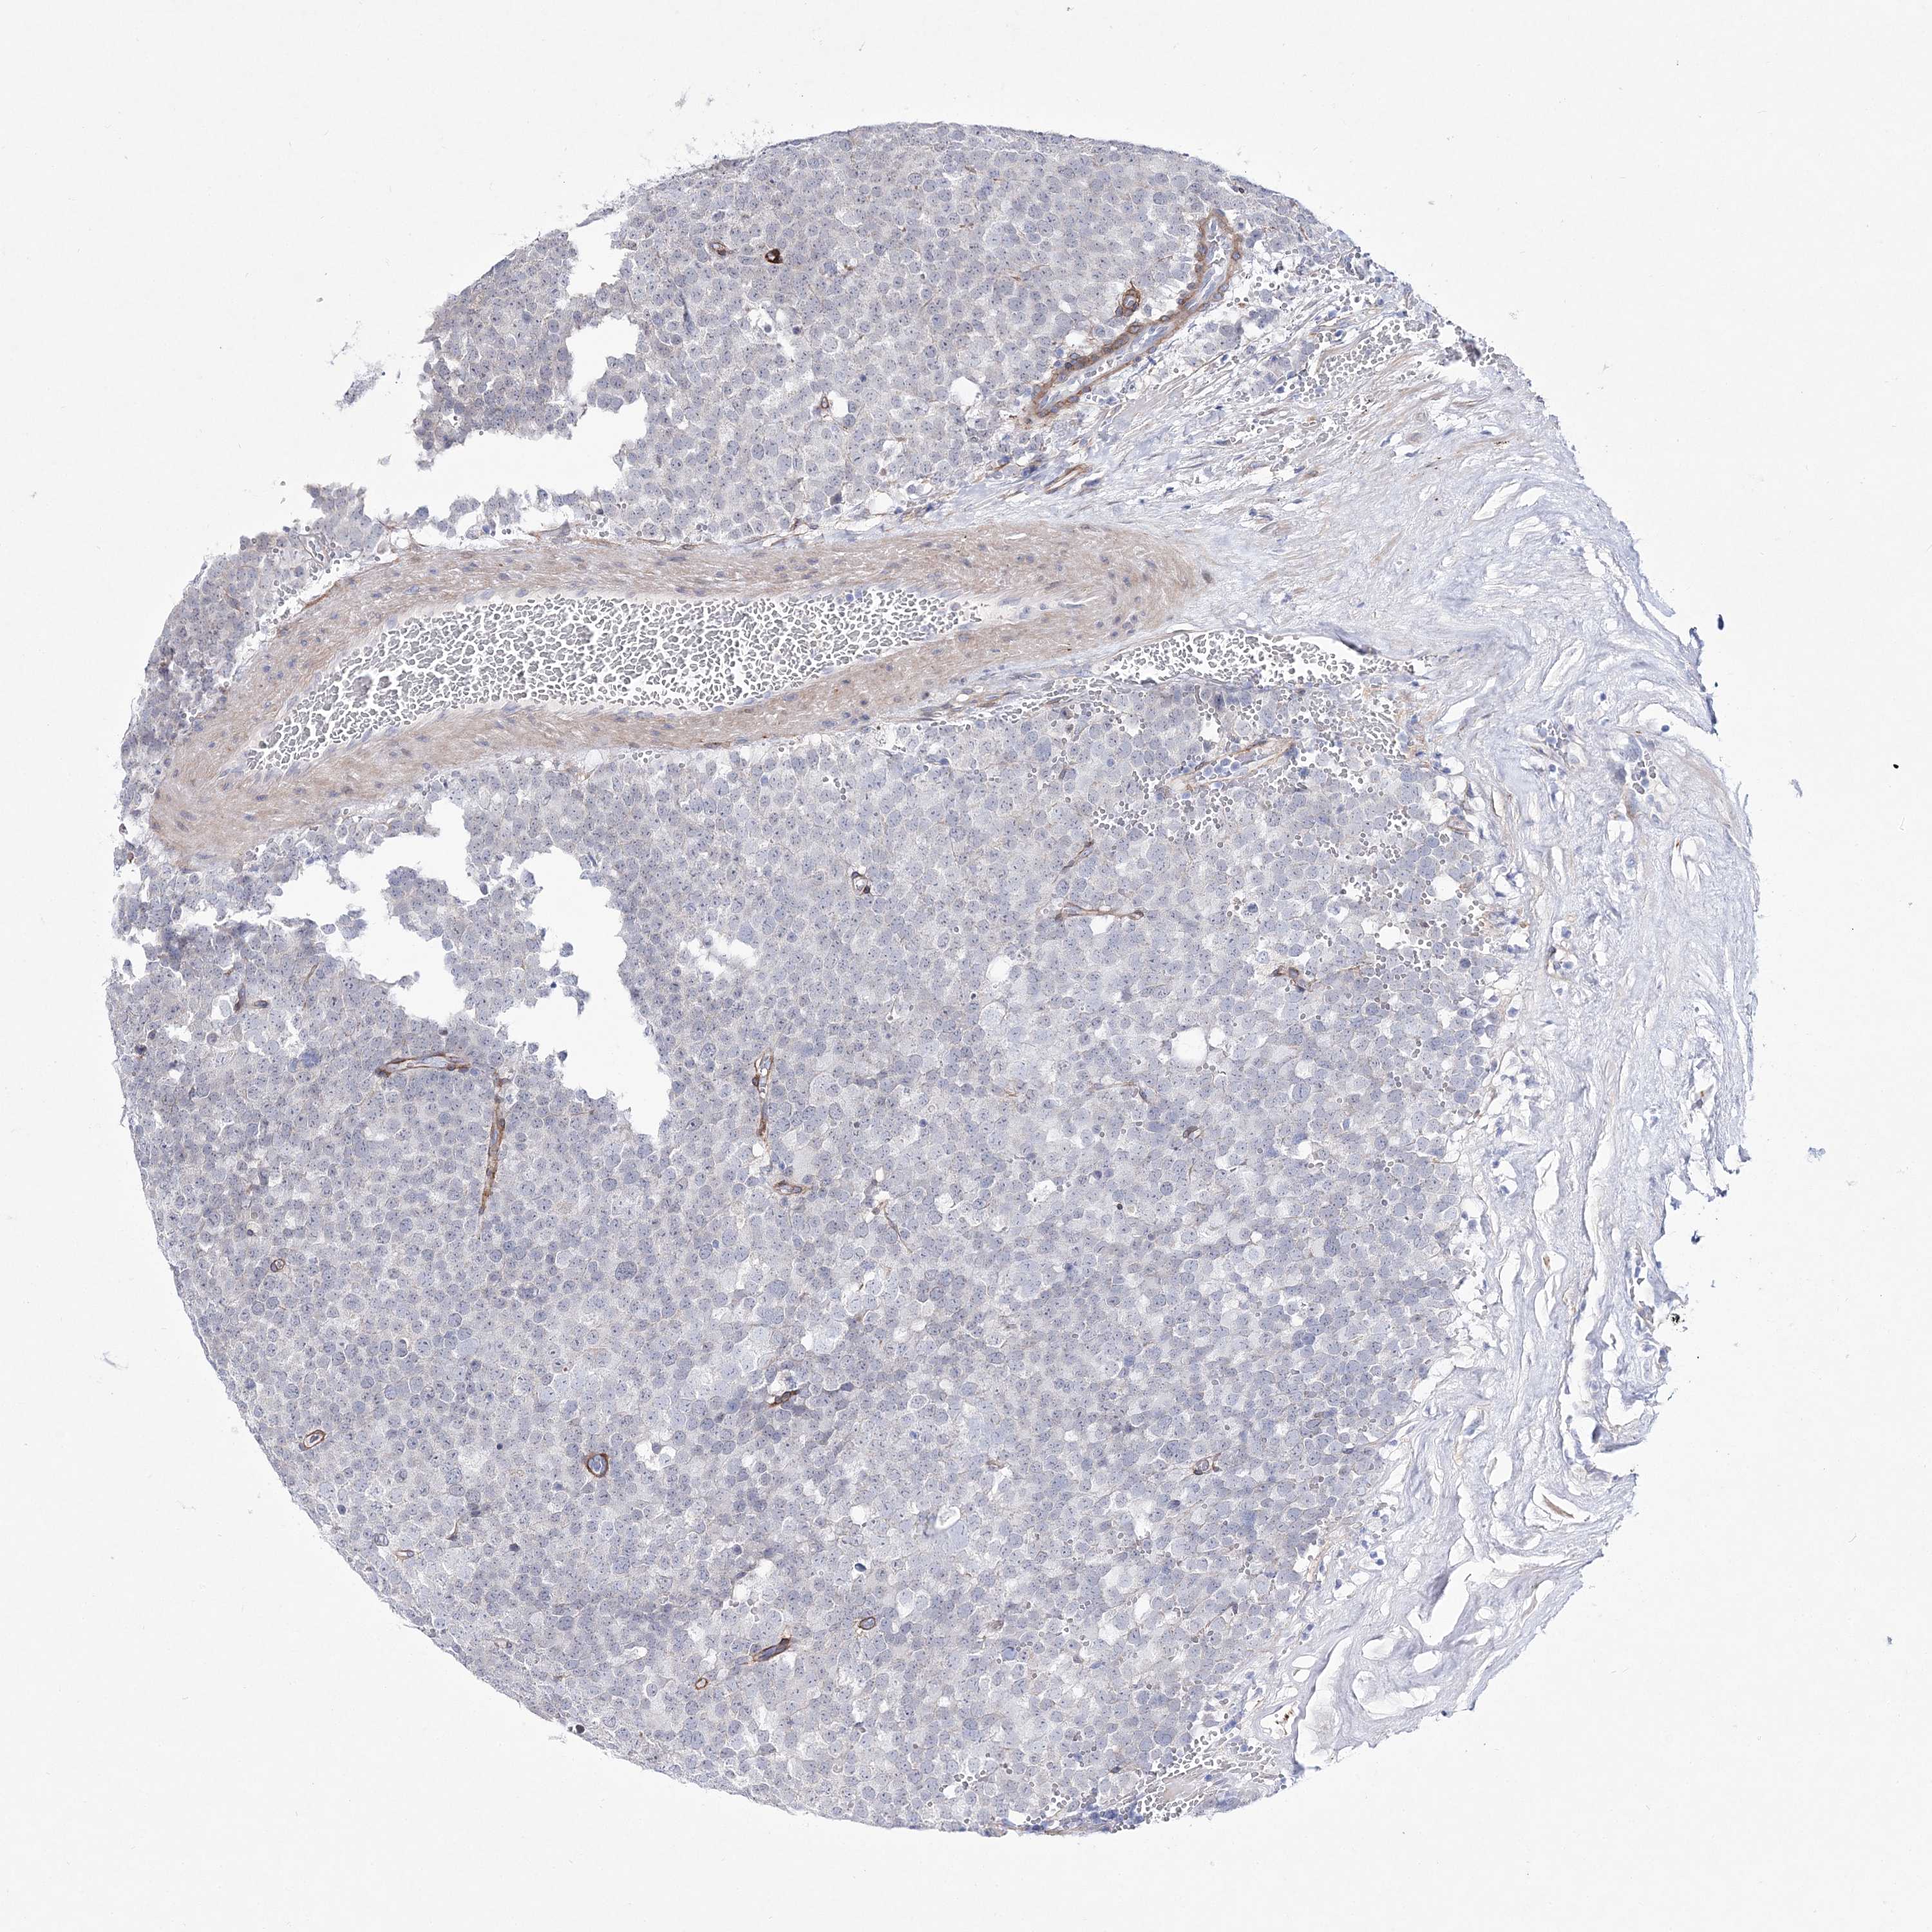

TESTIS CANCER - Protein expressioni

A mouse-over function shows sample information and annotation data. Click on an image to view it in a full screen mode. Samples can be filtered based on level of antibody staining by selecting one or several of the following categories: high, medium, low and not detected. The assay and annotation is described here.

Note that samples used for immunohistochemistry by the Human Protein Atlas do not correspond to samples in the TCGA dataset.

Antibody stainingi

Antibody staining in the annotated cell types in the current human tissue is reported as not detected, low, medium, or high, based on conventional immunohistochemistry profiling in selected tissues. This score is based on the combination of the staining intensity and fraction of stained cells.

Each image is clickable and will lead to virtual microscopy that enables deeper exploration of all samples and also displays staining intensity scores, fraction scores and subcellular localization as well as patient and tissue information for each sample.

Antibody HPA032148

Antibody HPA057356

Carcinoma, Embryonal, NOS

Seminoma, NOS

Teratoma, malignant, NOS